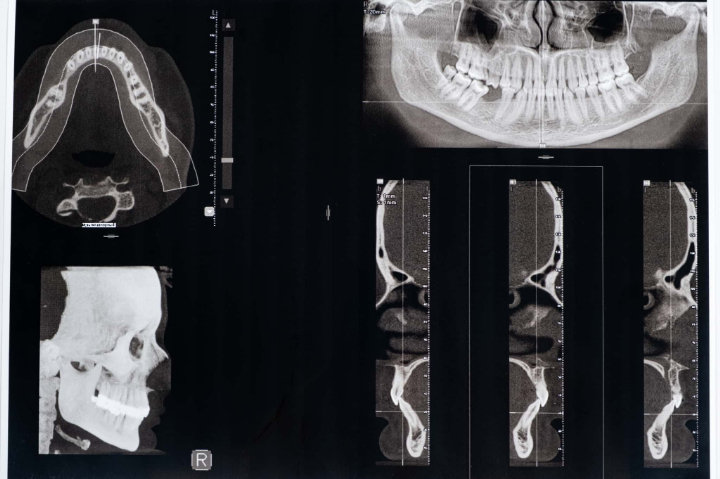

噛み合わせの調整

噛み合わせに問題がある場合は、調整を行うことで顎関節症の症状を和らげられることがあります。具体的には、歯の高さをわずかに削ってバランスを整えたり、詰め物や被せ物を調整したりします。

歯の一部を調整することで、顎への負担を減らし、症状の改善を図ります。ごくわずかな調整で済むことが多いため、身体への負担も少ないのが特徴です。